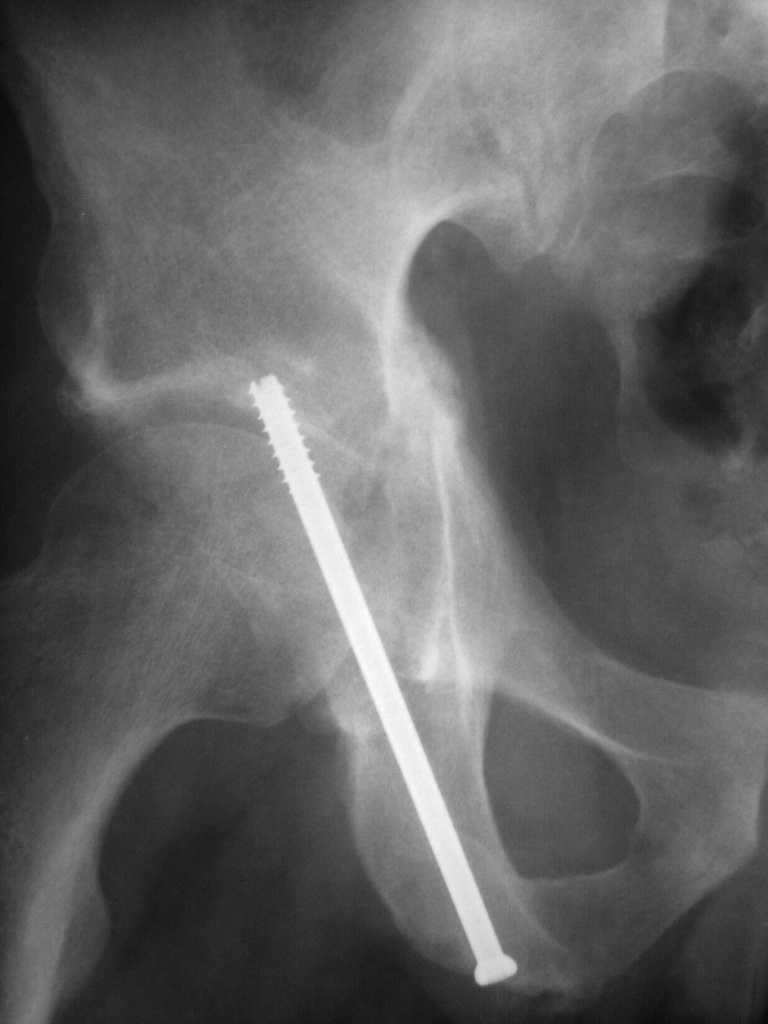

Yordan! In this case position of bone fragments is quite good. We

prefer to use miniinvasive technique. We fix posterior column by can. screw and put 3mm pin with distal thread to the anterior column. Next day after the surgery he may start walking with crutches. 3 month after the surgery we remove the pin. In cases of maleolar fractures we use

Sending exampl pict.